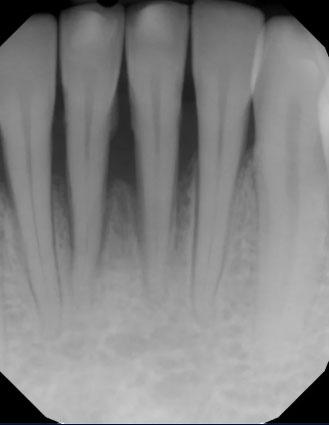

The dental X-ray shows the front teeth (anterior teeth) with clearly visible roots and surrounding bone. The bone level around the roots appears reduced and uneven, especially near the root tips. This finding can indicate early bone loss or a low-grade infection around one or more teeth.

There are no visible crowns or restorations in this area, which helps focus the evaluation on bone and root health.

This X-ray highlights bone changes around anterior teeth, which often progress without pain. Early dental evaluation and monitoring are essential to protect both function and appearance.